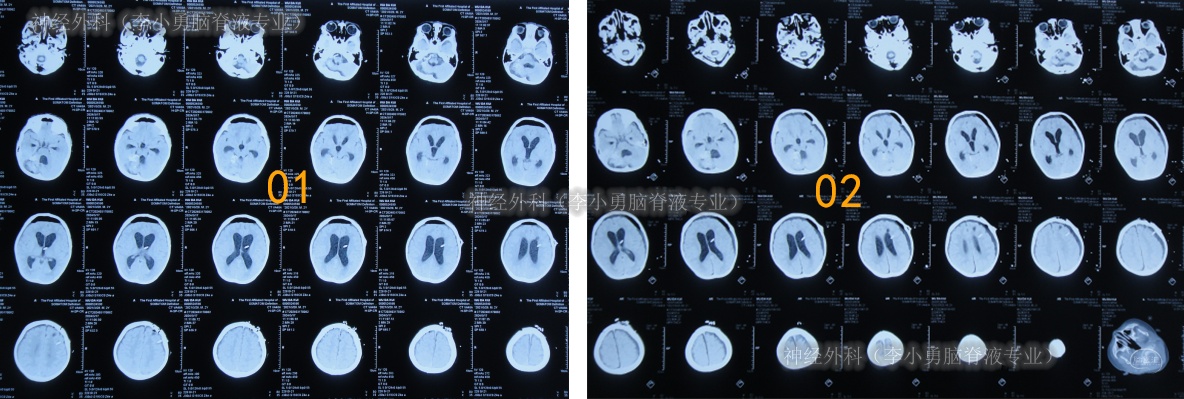

入院后17天即2024年6月19日,变得能经口进食拔除鼻饲管(图-12);查头颅CT示引流术后状态(图-13)。

图-13:2024年6月19日头颅CT

按计划于2024年8月29日,进行了脑室腹腔分流术(图-18)。

图-18:2024年8月29日头颅CT